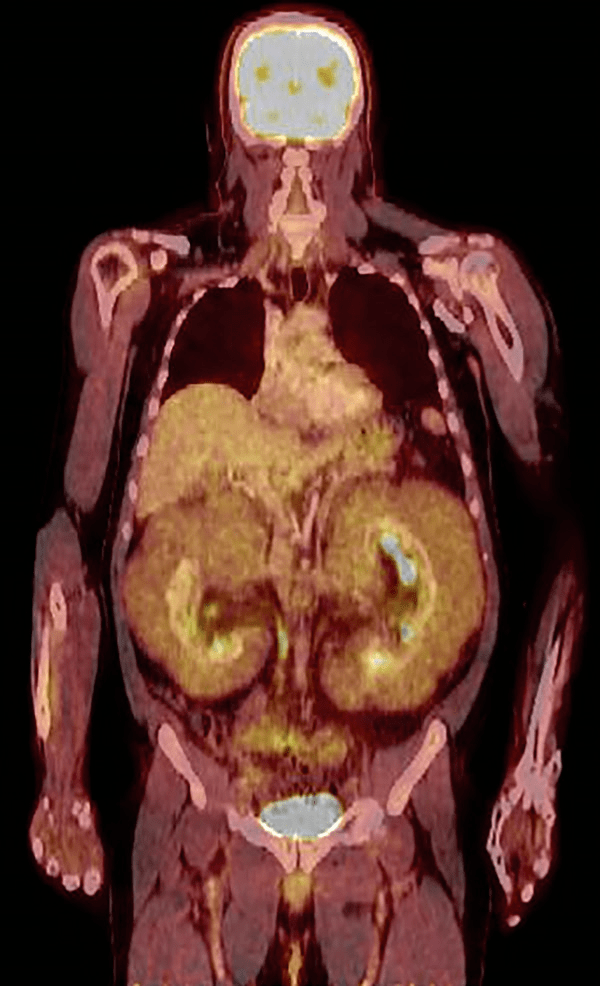

Figure 2:

18F-FDG PET/CT扫描显现肾周肿块洋溢性细微放射性摄取、肝脏向上移位,其他部位无累及。